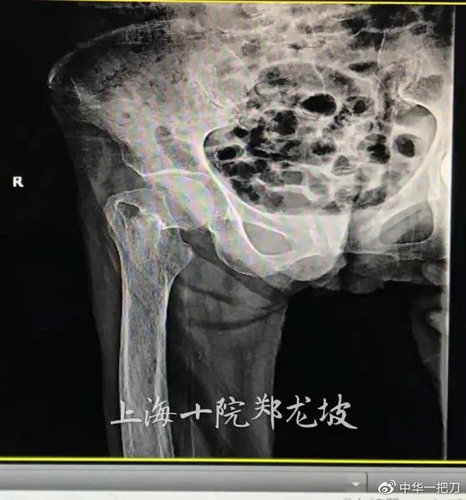

造成股骨头坏死的原因有不少,比如长时间的每天喝很多酒或者服用激素药物、长期从事比较劳累的工作都能引起股骨头坏死,因为这些原因造成股骨头的血液不循环,血液不流通,在治疗的时候也要在血液方面着重治疗。